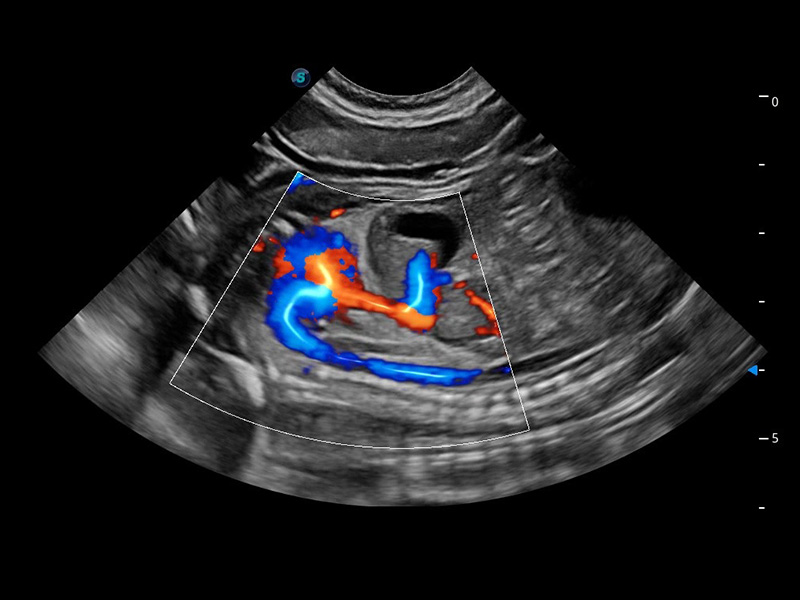

(犬)四腔心血流

在传统二维血流成像的基础上,呈现血流的立体感,具有动感的生命力之美。精确区分不同血管的空间关系,提高了血流的视觉敏感性。